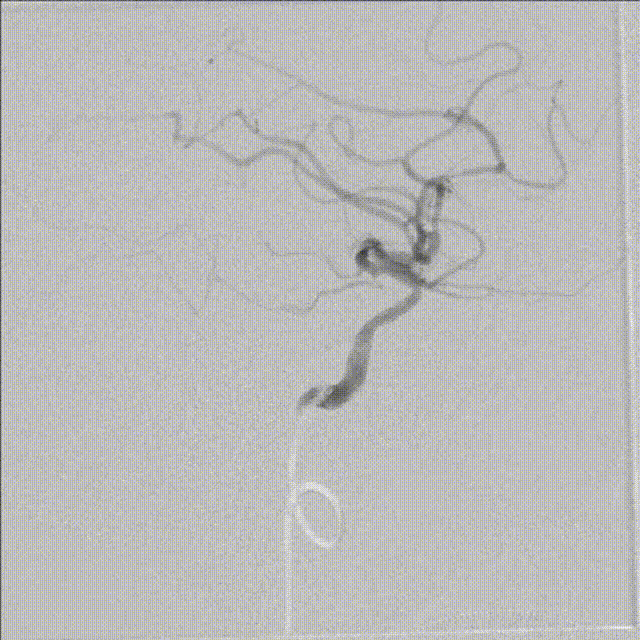

经6F中间导管,微导丝到位后引导Fastunnel®输送型球囊扩张导管到位至左侧大脑中动脉狭窄部位。

Fastunnel®输送型球囊扩张导管打压成形扩张狭窄病变部位,压力8atm,随后造影可见成形满意。

撤出微导丝后,经Fastunnel®输送型球囊扩张导管送入3.0mm*16mm NeuroStellar®颅内支架,支架到位后调整释放张力后定位支架。

术中缓慢释放NeuroStellar®颅内支架头端后系统稳定,随后释放至支架尾端,造影提示支架打开满意,贴壁满意。